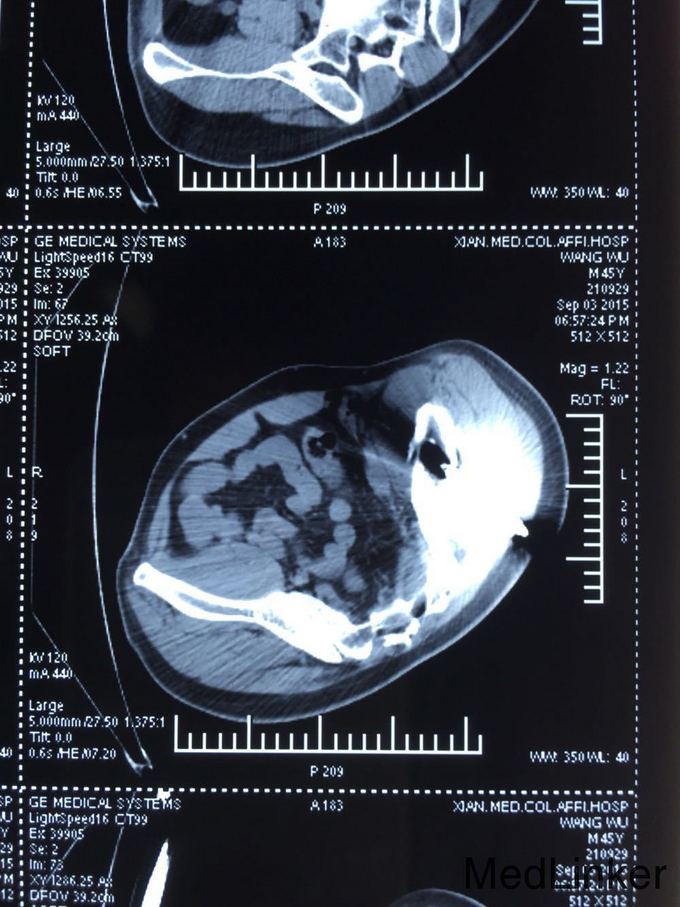

病例特征:男性患者,30岁。 主诉:外伤后腰腹部疼痛伴出血1小时。 现病史:患者于1小时前不慎从高处坠落受伤,伤后钢筋样异物从左腰髂部刺入直达左下腹壁,未穿透腹壁,致其疼痛、出血,无意识障碍,无恶心、呕吐,无胸闷、气短,由120急送至我院急诊科,急诊科给予补液等对症治疗,予急诊科就诊过程中由“消防员”将体外多余“钢筋样异物”去除;急查腹部CT示:1.盆腔见条状金属致密物,从左臀穿向前下腹部皮下,长约28cm;2.左侧腹膜周围见少许渗出性改变;3.左侧精索肿胀,其内气体影,左侧睾丸肿胀;4.左侧髂骨骨折。遂以“钢筋穿透伤”收住我科。自受伤以来,未进饮食,精神差,小便正常,未解大便。 既往病史:否认肝炎、结核、疟疾病史,否认高血压、心脏病史,否认糖尿病、脑血管疾病、精神疾病史,否认手术、外伤、输血史,否认食物、药物过敏史,预防接种史不详。

查体:T:36.6℃,P:80次/分,R:19次/分,Bp:130/85mmHg。心肺未见明显异常,腹平坦,无腹壁静脉曲张,腹部柔软,无压痛、反跳痛,腹部无包块,左侧腰髂部近左臀部可见钢筋样异物刺入直达左下腹腹壁皮下,未穿透腹壁皮肤,左臀部皮肤裂伤伴出血,伤口处压痛,肝脾肋下未触及,左下腹压痛,Murphy氏征阴性,移动性浊音阴性,肝脾肾区无叩击痛,肠鸣音未见异常。 辅助检查:全腹部CT检查示:1.盆腔见条状金属致密物,从左臀穿向前下腹部皮下,长约28cm;2.左侧腹膜周围见少许渗出性改变;3.左侧精索肿胀,其内气体影,左侧睾丸肿胀;4.左侧髂骨骨折。